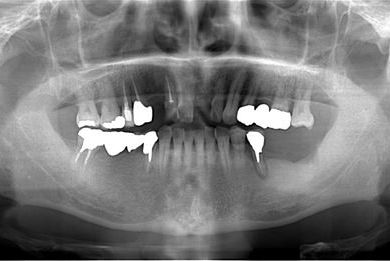

| 性別/年齢 | 男性 / 65歳 | ||||||||||||||||||||||||||||||||

| 主訴 | 右奥歯の義歯の不具合について相談したい。 | ||||||||||||||||||||||||||||||||

| 治療方針 | 抜歯と同時にインプラント埋入を行い、治療期間を短縮する。 | ||||||||||||||||||||||||||||||||

| 治療内容 | インプラント5本(抜歯即日スピードインプラント、テンポラリーインプラント)、メタルボンドセラミッククラウン5本 | ||||||||||||||||||||||||||||||||

| 総治療費 | 1,913,100円 | ||||||||||||||||||||||||||||||||

| 治療期間 | 1年9ヶ月 |